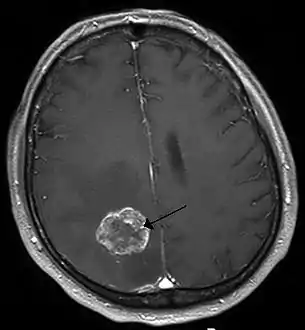

Imaging

Medical imaging plays a central role in the diagnosis of brain tumors. Early imaging methods – invasive and sometimes dangerous – such as pneumoencephalography and cerebral angiography have been abandoned in favor of non-invasive, high-resolution techniques, especially magnetic resonance imaging (MRI) and computed tomography (CT) scans, though MRI is typically the reference standard used.[37] Neoplasms will often show as differently colored masses (also referred to as processes) in CT or MRI results.

- Benign brain tumors often show up as hypodense (darker than brain tissue) mass lesions on CT scans. On MRI, they appear either hypodense or isointense (same intensity as brain tissue) on T1-weighted scans, or hyperintense (brighter than brain tissue) on T2-weighted MRI, although the appearance is variable.

- Contrast agent uptake, sometimes in characteristic patterns, can be demonstrated on either CT or MRI scans in most malignant primary and metastatic brain tumors.

- Pressure areas where the brain tissue has been compressed by a tumor also appear hyperintense on T2-weighted scans and might indicate the presence a diffuse neoplasm due to an unclear outline. Swelling around the tumor known as peritumoral edema can also show a similar result.